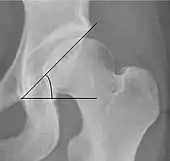

| Measurement | Image | Target | Normal value |

|---|---|---|---|

| Acetabular depth ratio | ![]() |

Deepness of acetabulum. | >250

|

| Center-edge angle of Wiberg | ![]() |

The superior-lateral coverage of the femoral head. | |

| Reimer's migration index[9] | ![]() |

The percentage of the femoral head that lies outside of the acetabular roof. It is also called the femoral extrusion index. | <25% |

| Tönnis angle | ![]() |

Slope of the sourcil (the sclerotic weight-bearing portion of the acetabulum) | 0 to 10°

| Caput-sourcil angle[12] | ![]() |

Superior to the Tönnis angle in cases without joint space narrowing or subluxation.[12] The medial point of the sourcil is defined as being at the same height as the most superior point of caput femoris. | −6 to 12°[12]

| Sharp angle | ![]() |

Acetabular slope | <45°

| Cervical diaphyseal angle | ![]() |

The angle formed between the femoral neck and femoral diaphysis | 120° to 140°